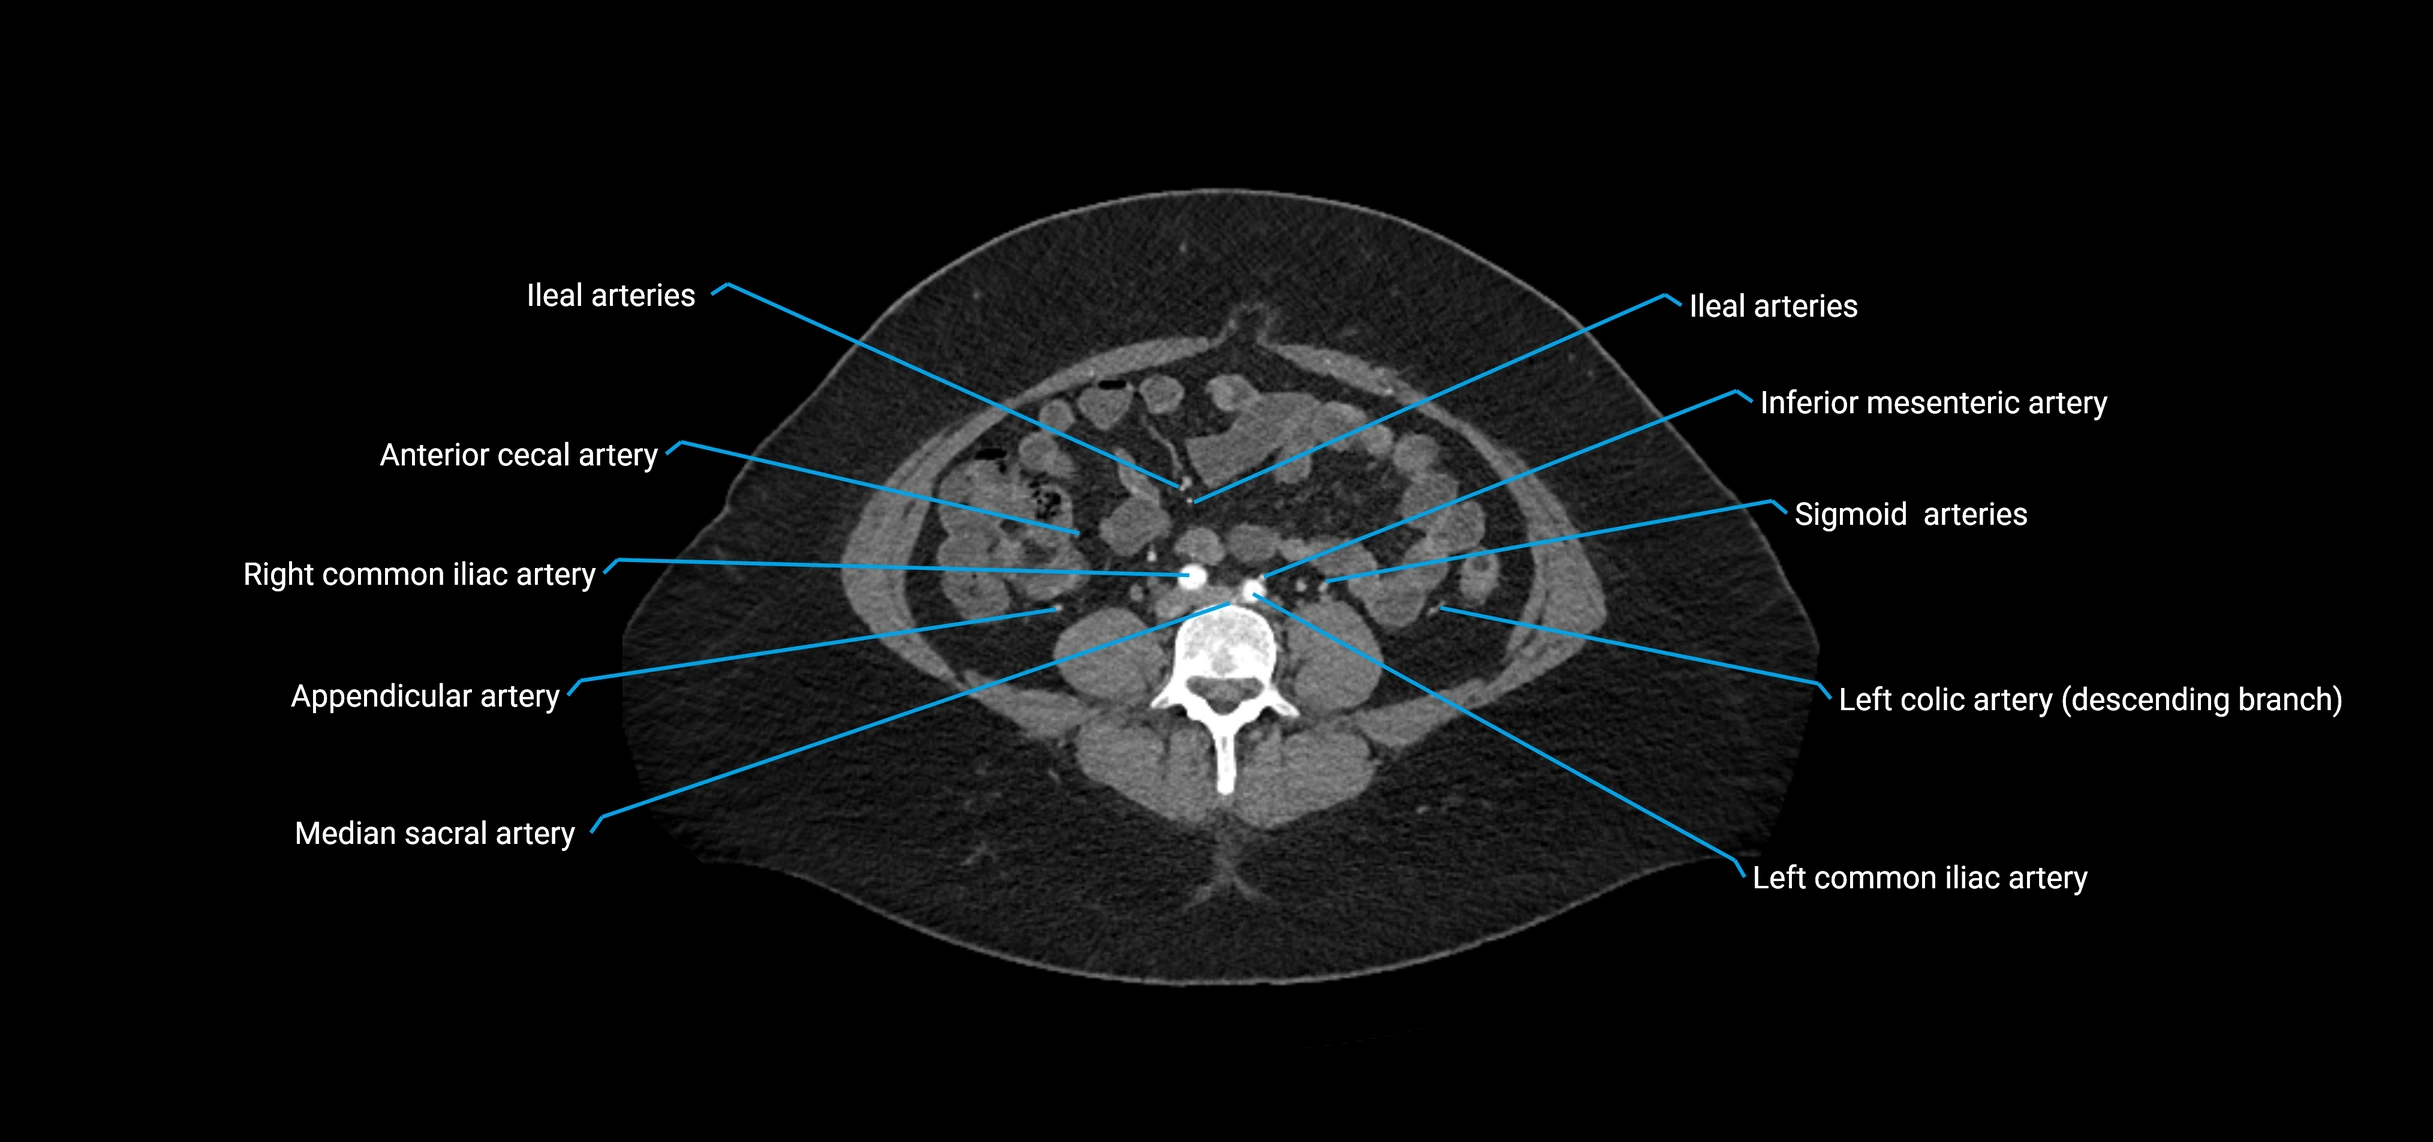

• Unpaired visceral branches: celiac trunk, superior mesenteric artery (SMA), inferior mesenteric artery (IMA)

• Paired visceral branches: middle suprarenal arteries, renal arteries, gonadal arteries (testicular or ovarian)

• Parietal branches: inferior phrenic arteries, lumbar arteries, median sacral artery

• Terminal branches: right and left common iliac arteries

Contrast-enhanced CT (CTA):

• Gold standard for abdominal aortic imaging

• Provides excellent detail of lumen, wall, aneurysm, thrombus, and branch vessels

• Multiplanar and 3D reconstructions help in aneurysm measurement, stent graft planning, and dissection evaluation

• Detects acute rupture, traumatic injury, or occlusion with high sensitivity